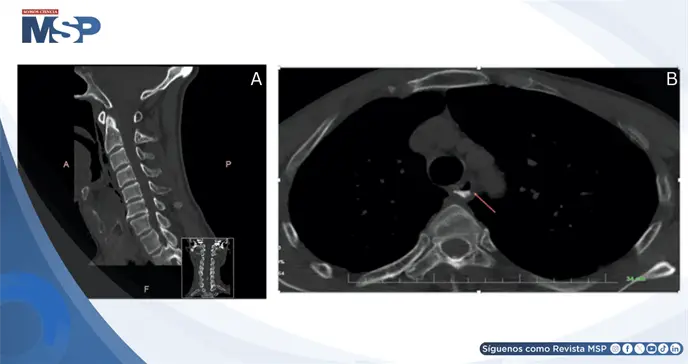

Los estudios de imagen fueron fundamentales para el diagnóstico. La tomografía computarizada de columna cervical mostró cambios degenerativos sin fracturas, mientras que la esofagografía con contraste de gastrografina demostró irregularidades en la pared esofágica proximal con extravasación del medio de contraste hacia el espacio extraluminal.

Se identificaron densidades de gas en los espacios retrofaríngeo y paravertebral, confirmando la perforación esofágica. La laringoscopia directa bajo anestesia general permitió visualizar una ruptura de 2.5 cm en la pared posterior de la hipofaringe.